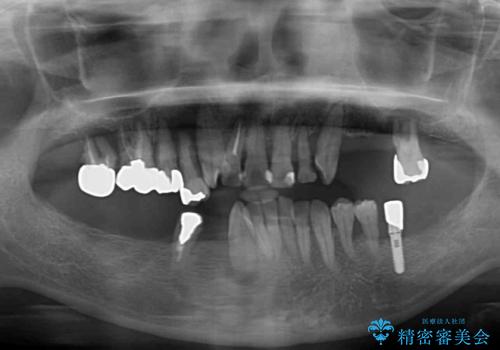

- 歯周病を放置したことで奥歯が抜け、前歯も痛くなってきたとのことで来院された患者様です。

奥歯はほとんどを抜歯しなければならない状態であり、抜歯をせずに済む歯も歯周外科処置や矯正治療を行う必要がある状態でした。

歯を抜かないといけない部分はインプラントとオールセラミッククラウンにより咬合を回復させ、歯周外科処置を行う歯については、同じくオールセラミッククラウンにて補綴治療を行うこととしました。

外科処置を多く行ったため、その待ち時間が長くかかり、さらには途中矯正治療も行なったので、治療期間は長期間となりました。